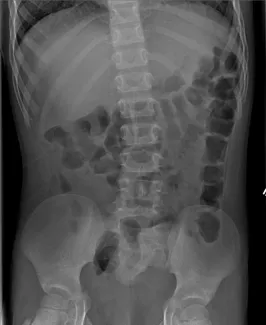

X-ray of clean colon

X-ray of constipated colon

Abdominal Xrays are necessary to evaluate the effectiveness of the laxative or enema therapy and to identify the amount of stool in the colon. These will be done at each office visit.